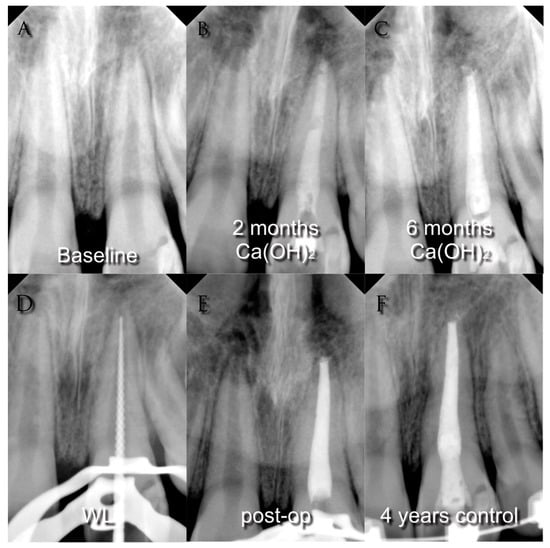

Since the 1960s, the procedure indicated to treat immature permanent teeth with loss of vitality was apexification [,], a technique that aims to obtain a calcified apical barrier that permits the canal to be filled in a conventional way afterward [], see Figure 1.

Figure 1.

(A) Pre-operative radiograph of a young necrotic upper left central incisor with periapical lesion; (B) radiograph after two months medication with calcium hydroxide; (C) radiograph after six months medication with calcium hydroxide; (D) working length determination; (E) post-operative radiograph; (F) four-years control radiograph.